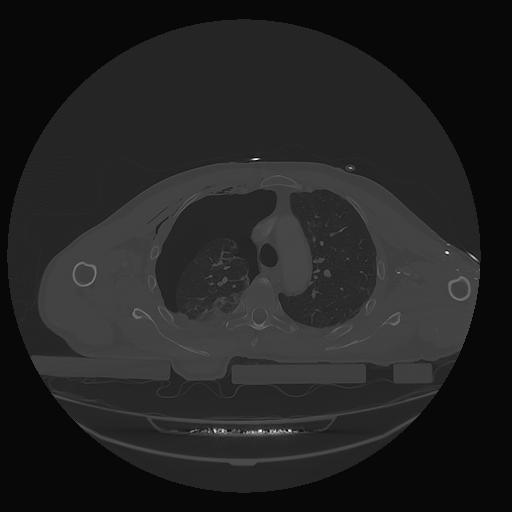

31 PULMON,CE,Vol,1.0,PULMON,,